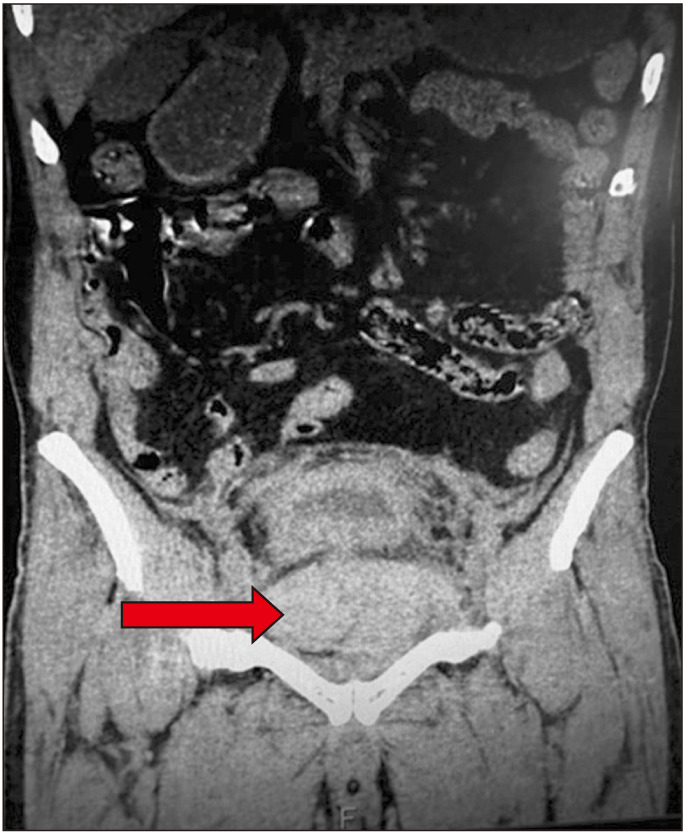

Pelvic hematoma post prostatic urethral lift: A need to be vigilant in high-risk patients.